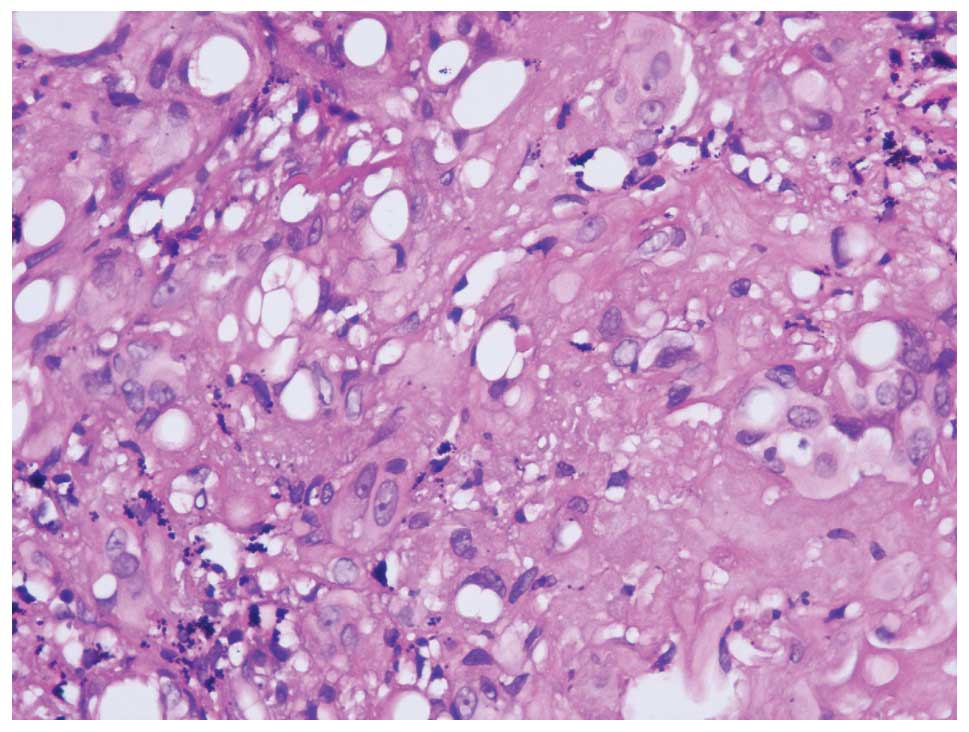

Treatment of pulmonary epithelioid hemangioendothelioma with combination chemotherapy: Report of three cases and review of the literature

No standard therapy for pulmonary epithelioid hemangioendothelioma (PEH) has yet been established due to the rarity of the disease, the lack of clear standards for treatment and the partial‑to‑complete spontaneous regression. This report describes three cases of PHE manifested as bilateral intrapulmonary masses with an initial diagnosis conducted by thoracoscopic lung biopsy. These patients demonstrated a partial response to combination chemotherapy with carboplatin, paclitaxel, bevacizumab or endostar, and an improvement in clinical status. Furthermore, we reviewed the literature regarding such patients who received chemotherapy and immunotherapy; this indicated that patients with PEH demonstrated a good partial response to chemotherapy with carboplatin, paclitaxel, bevacizumab, thalidomide and α‑interferon. Overall, combination chemotherapy regimens may hold therapeutic potential for the treatment of this rare disease.

Figure 3